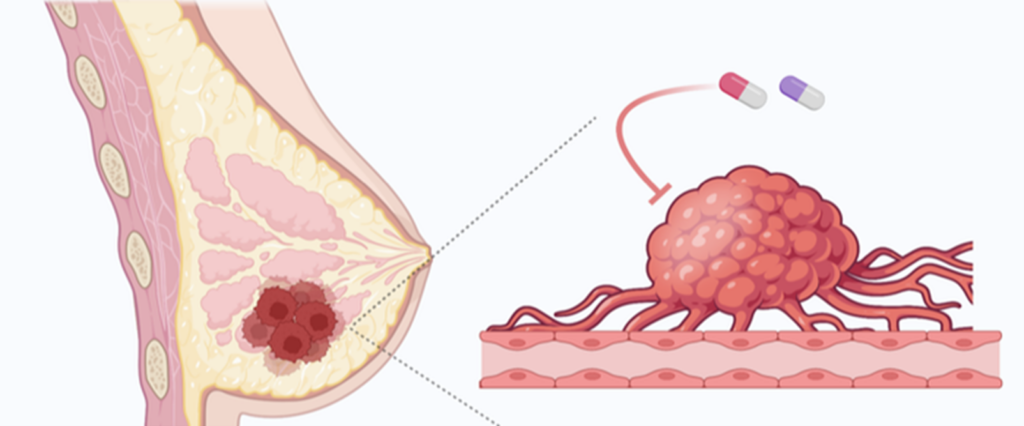

Meme Kanseri Tedavisi

Meme kanseri tedavisi ve meme rekonstrüksiyonu, oldukça karmaşık bir süreçtir ve bazı durumlarda ilaç tedavileri veya diğer tıbbi müdahaleler gerekebilir.

Tamoksifen, özellikle hormon reseptör pozitif meme kanseri tedavisinde kullanılan bir ilaçtır. Hormon reseptör pozitif meme kanseri, östrojen ve/veya progesteron hormonlarına duyarlı olan kanser türüdür. Tamoksifen, bu hormonların kanser hücrelerinin büyümesini teşvik etmesini engelleyerek çalışır. Bu nedenle, hormon reseptör pozitif meme kanseri olan hastalarda tamoksifen, kanserin tekrarlama riskini azaltmak ve tedaviyi desteklemek için kullanılır.

Aspirin, kan pıhtılarını önlemek ve kan akışını iyileştirmek için kullanılan bir ilaçtır. Meme rekonstrüksiyon ameliyatları gibi büyük cerrahi işlemler sonrası kan pıhtılarını önlemek amacıyla aspirin kullanılabilir. Ancak, aspirinin kullanımı öncesinde ve sonrasında, bir cerrah veya doktor tarafından yönlendirilmelidir. Aspirinin kanama riskini artırabileceği ve bazı durumlarda ameliyat sonrası kanamalara yol açabileceği unutulmamalıdır.